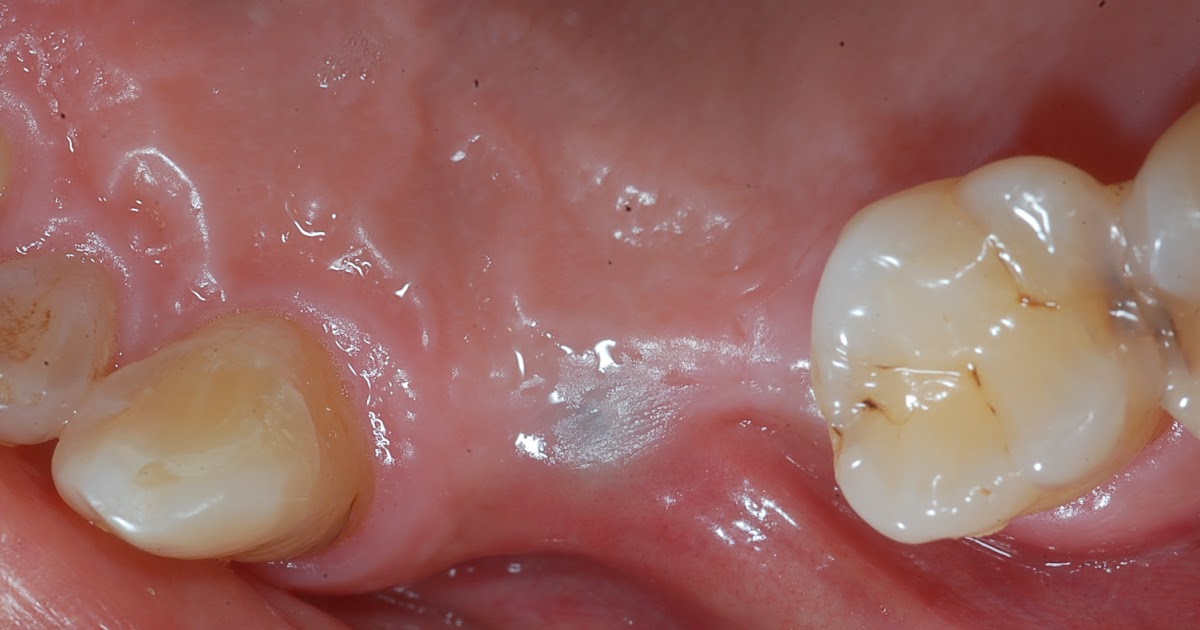

Dental implant professional 2nd surgery for implants exposure via Dental Implant Exposed if you've had your dental implant for a long time such as many years, the implant screw fixture showing near the gums could be normal. As with any surgery, healing can be uncomfortable and irritating. when can you resume normal activities? Understanding the underlying causes and. Over time, it's not unusual for implants to slowly experience very mild. Dental Implant Exposed.

Dental Implant Exposure Ryan Lanman DDS, MSD Dental Implant Exposed if you've had your dental implant for a long time such as many years, the implant screw fixture showing near the gums could be normal. These are all questions that come up when getting a dental implant for the first time. Scott froum looks at why this can happen and shares treatment options. Over time, it's not unusual for. Dental Implant Exposed.